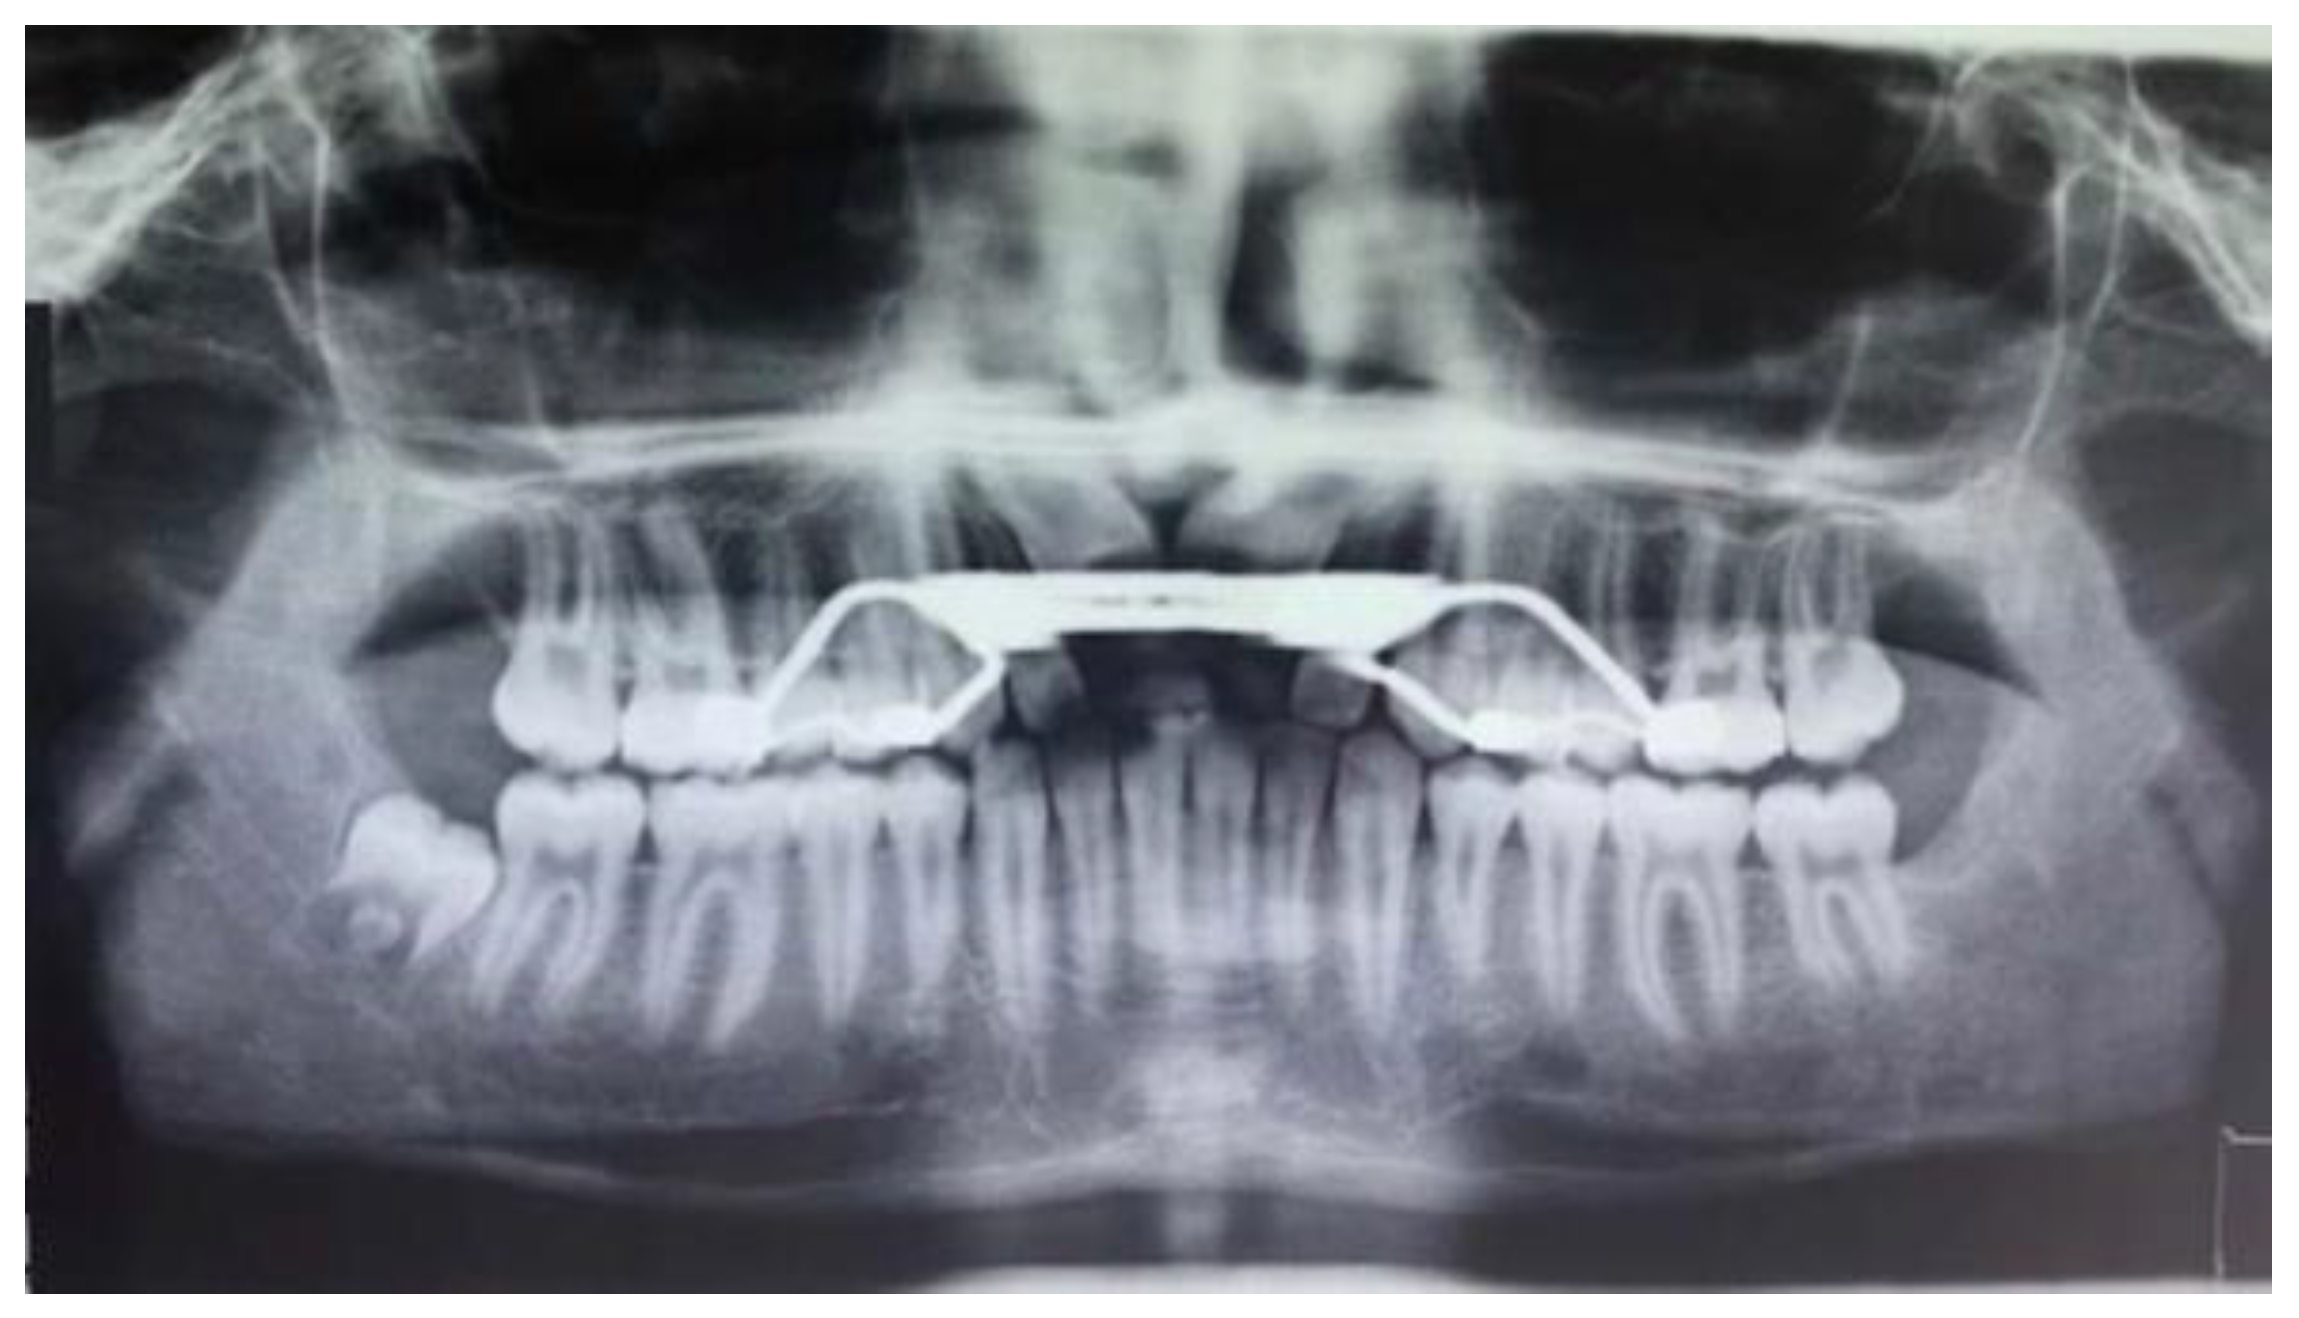

- Ortopanthomography X-ray (OPG X-ray) to evaluate the problem in relation to the entire arch, adjacent tooth and the staging of the eruption of the other dental elements.

3. Results